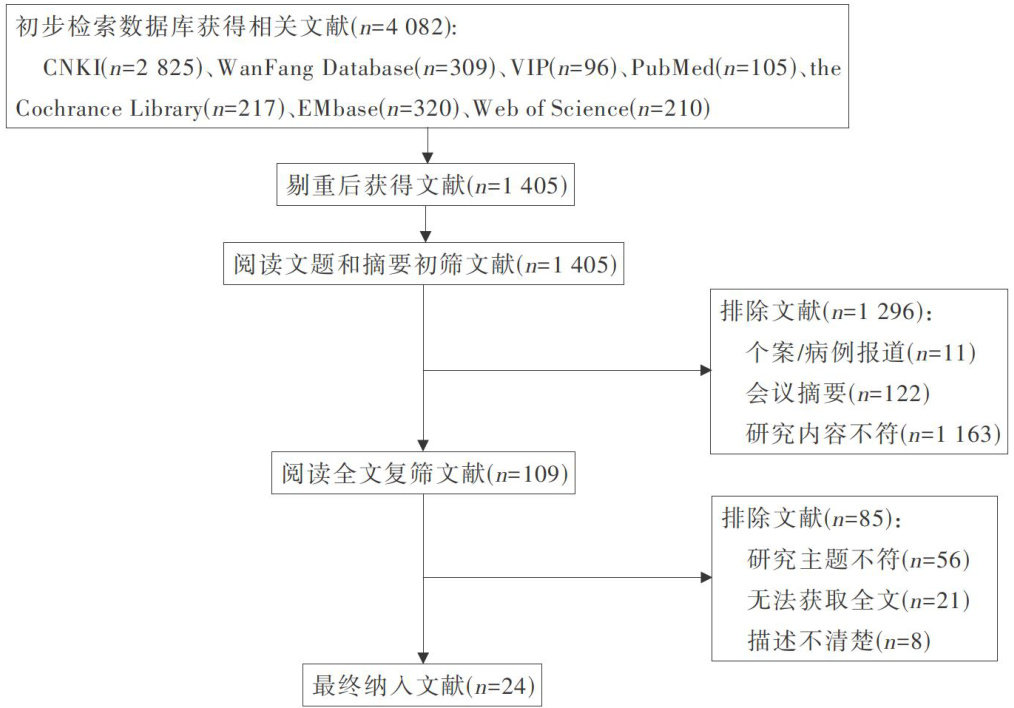

科研论著 | 生活方式干预对心血管代谢性共病病人影响的Meta分析

科研论著 | 生活方式干预对心血管代谢性共病病人影响的Meta分析